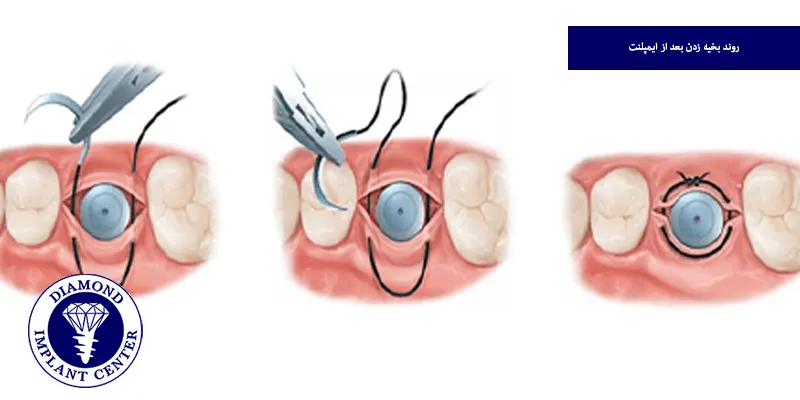

روند بخیه زدن بعد از ایمپلنت

پس از قرار دادن ایمپلنت در استخوان فک، جراح لثه را به دقت در محل برش، بخیه زده تا زخم پوشانده شود و برای این کار، از نخ بخیه مناسب استفاده میشود تا لثه به خوبی در کنار ایمپلنت ثابت بماند و از باز شدن زخم جلوگیری شود، جراح با بخیههای ریز و منظم، لثه را به آرامی به هم دوخته تا فشار بر روی بافت کم شود و خونرسانی بهبود یابد، بسته به نوع بخیه قابل جذب یا غیرقابل جذب، ممکن است بخیهها پس از چند روز جذب شده یا نیاز به کشیدن داشته باشند و این مرحله کلیدی به بهبودی سریعتر و جلوگیری از عفونت کمک میکند.

بخیههای ایمپلنت دندان به دلیل حساسیت و اهمیت تثبیت ایمپلنت در استخوان فک، معمولا از نخهای خاص با استحکام و دوام بیشتر استفاده میکنند تا زخم به خوبی بسته و در جای خود ثابت بماند، همچنین در ایمپلنت، دقت و ظرافت بخیه زدن بالاتر است تا فشار اضافی به بافت وارد نشود و روند جوش خوردن ایمپلنت با استخوان به خوبی انجام شود.